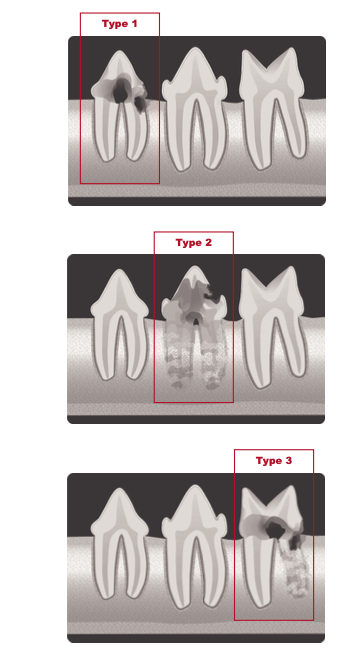

Классификация по типам рентгенологических проявлений резорбции зубов1 (фото 17):

Тип 1: наблюдается потеря альвеолярной кости, примыкающей к области резорбции зуба, на других участках зуба сохраняется нормальное пространство периодонтальной связки.

Тип 2: потеря пространства периодонтальной связки и цемента зуба из-за сращения корня зуба с альвеолярной костью (дентоальвеолярный анкилоз), резорбирующаяся структура зуба выглядит менее рентгеноконтрастно, чем неповрежденный зуб.

Тип 3: комбинация типов 1 и 2.